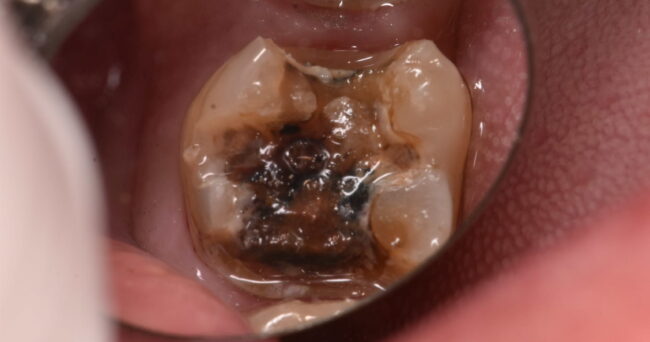

今回はわかりやすいです。下の画像をご覧ください

外すとこうなります。

ちなみに、オレンジっぽいところは柔らかく、虫歯が残っている部分です

長期間たって、銀歯の周りの色が変になっているものは、大抵こんな感じです。

部分的な銀歯はこうなるリスクが高いので、ご注意下さい。